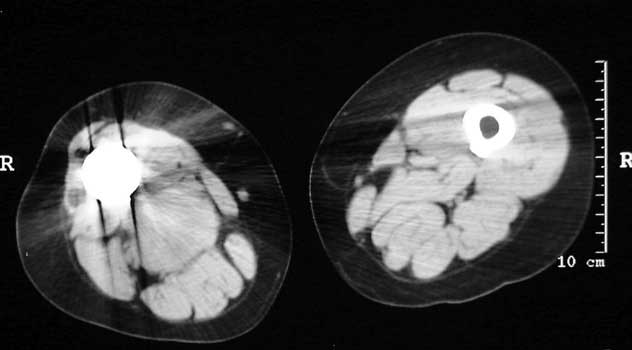

Mass in patient with modular endoprosthesis placed after resection of femur for osteosarcoma. Axial (fig A) and coronal reformatted images (fig B) clearly demonstrate mass adjacent to modular endoprosthesis. 14 gauge core needle biopsy performed under CT guidance (fig C) demonstrated recurrent osteosarcoma